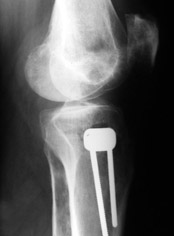

Картинки - в приложении.Будут вопросы - готов ответить.

Ещё картинка - схема. Хотя у Соломина всё написано.

Вот ещё картинки, которые отправлял в Ортопод. Коррекция кривизны и удлинение на 3 см.